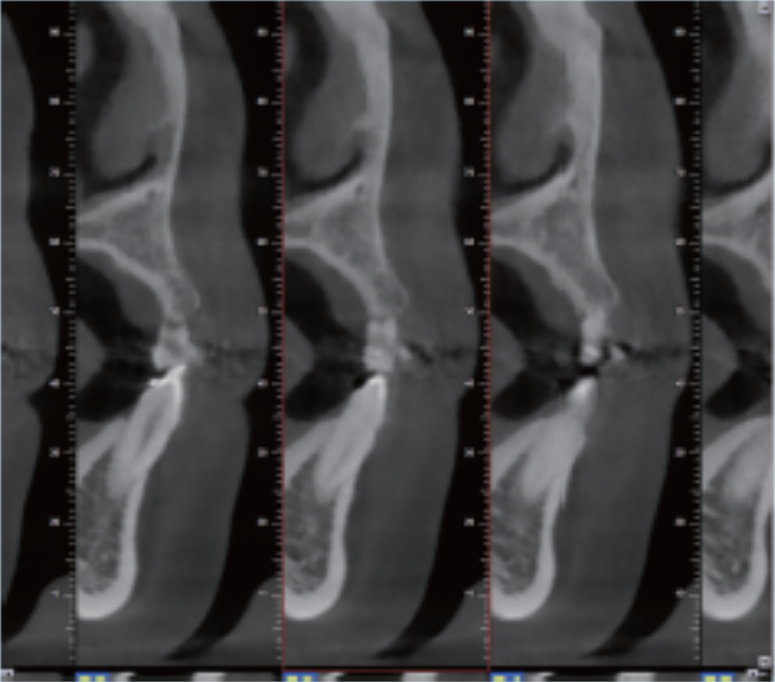

方法:患者轻咬合状态进行CBCT(NewTomTM,Verona,Italy)扫描,扫描结果以DICOM(digitalimagingandcommunicationinmedicine)格式导出。CBCT显示:左上乳尖牙牙根周围牙槽骨吸收,可用骨高度约15mm,颊舌径宽约6mm。

口内扫描利用3shape扫描制作伴有咬合面记录的数字化诊断印模。采用非接触式光学口内印模技术,对邻牙及正畸配件无损伤。将CBCT数据以DICOM格式导入3shape软件,进行颌骨三维重建,根据颌骨的三维解剖结构和咬合关系,设计种植的位置、角度、数目及深度,在此设计方案上利用3shape软件设计种植导板及个性化基台和临时牙。